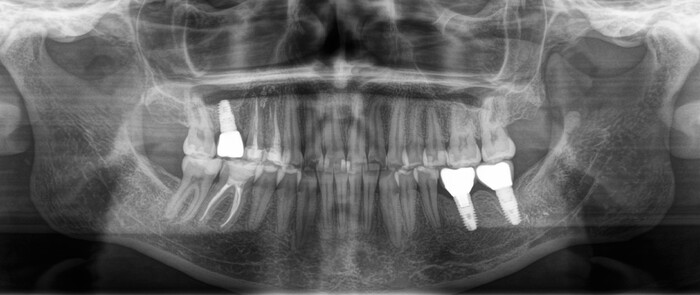

Проходит еще полтора года и пациентка вдруг приходит на осмотр с жалобами на подвижность коронки в области той самой 6ки, с которой мы начали. Сначала показалось, что просто раскрутился винт, фиксирующий коронку к имплантату.

И тут начинается самое интересное. Что такое абатмент мы выяснили из картинки выше, это переходный элемент между коронкой и имлпантатом. Так вот по всем технологиям и нормам он должен быть титановым. Как контрастирует титан на рентгеновском снимке вы можете заметить, посмотрев на имплантат. Видите разницу между 6м и 7м имплантатом?

Так вот абатмент, который вставляется в имплантат из другого материала. Вероятнее всего это кобальт-хромовый сплав. Такие штуки изготавливаются литьевым методом. Все мы знаем, что металл при нагревании расширяется, а остывая сжимается, дает усадку. Соединение имплантат- абатмент должно быть четким. Важны даже микроны. В данном случае наверняка была микроподвижность в этом соединении, высокая нагрузка на винт, в связи с чем он и сломался.

На рентгеновском снимке:

И вот эти проблемы дали о себе знать. Июнь 2023 года, спустя каких-то 5 лет после установки коронки на 7й нижний имплантат винт ломается и в нем.

Прикус:

За эти годы ситуация усугубилась, стираемость зубов прогрессировала.